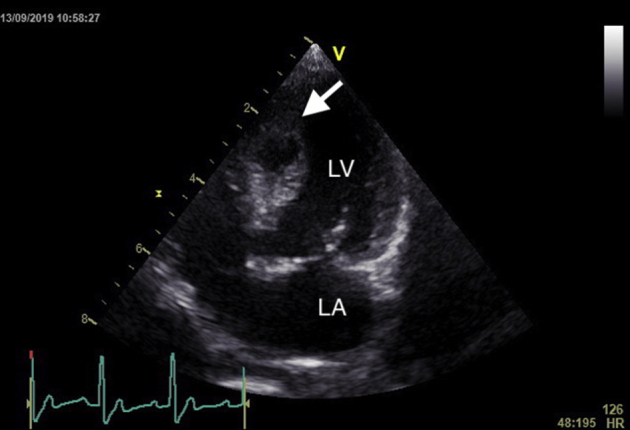

An 8-year-old, male, neutered, 4.6-kg Pomeranian cross dog was presented with a 5-month history of congestive heart failure (CHF) secondary to severe myxomatous mitral valve disease (MMVD), American College of Veterinary Internal Medicine (ACVIM) stage C.2 The dog underwent surgical MVR under CPB, with routine heparin anticoagulation. Immediate postrepair transesophageal echocardiography (TEE) suggested successful repair with mild residual mitral regurgitation. Protamine was administered after the dog was weaned off CPB uneventfully. Total CPB time was 111 min, and cross-clamp time was 70 min. Myocardial quiescence was achieved by the infusion of cardioplegia solution every 20 min, allowing electrochemical cardiac arrest. Approximately 6 hours postoperatively, acute hypotension was noted with a mean arterial blood pressure (BP) of 50 mm Hg. Bedside transthoracic echocardiography (TTE) revealed abnormal thickening of the interventricular septum (IVS), which measured 18 mm in diastole compared with 7 mm preoperatively. Multiple small (8 × 4 mm) oval-shaped anechoic mass lesions were evident diffusely throughout the IVS, compatible with IVSH (Figures 1A and 1B). The IVS was hypokinetic and thickened. There was also evidence of mild pleural effusion.

Figure 1.

TTE 6 hours after MVR, during period of hypotension. (A) Right parasternal long-axis view and (B) right parasternal short-axis view revealing multiple small IVSHs (arrow). LA, Left atrium; LV, left ventricle.